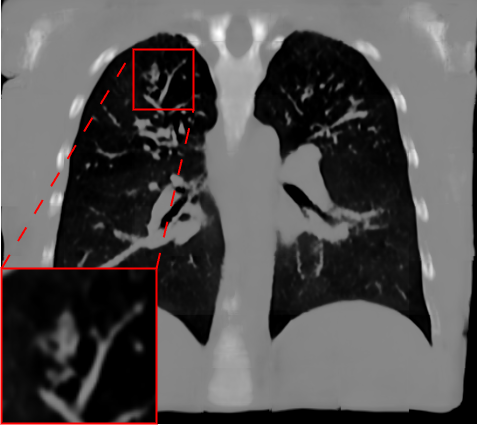

Fig. 2 presents a visual comparison of lung coronal sections from different models. The model using L1 loss results in blurred images, with particularly poor bone reconstruction. In contrast, the MedicalNet-based model produces sharper images but introduces artifacts in anatomical areas. Models based on AFP loss offer visually appealing results, with well-reconstructed anatomical bones and lung tissue. Additionally, only NaviAirway and HAL methods provide detailed bronchial reconstruction, as highlighted in the zoomed-in section.

To handle memory constraints during training and inference, we used a patch-based strategy. We experimented with multiple patch sizes, including and , and also used nnU-Net’s default adaptive windowing strategy (e.g. for thoracic cases). While larger patches provide more contextual information and generally improve reconstruction quality, the overall performance did not differ substantially from nnU-Net’s dynamic patching. Some visible artifacts in Fig.2 result from patch combination, especially in regions not covered by the segmentation network used for AFP supervision. For instance, when the AFP loss relies on the NaviAirway model, artifacts often appear outside the lung fields, as the network lacks anatomical guidance in those regions. However, these artifacts are purely visual and do not affect the downstream segmentation results or the quantitative metrics reported, which are detailed in the upcoming paragraph.

Table 1 presents a quantitative evaluation of the model’s performance on lung MR to CT synthesis, based on the MAE, SSIM, Dice score, and NSD between synthesized and ground truth CT images. The adapted nnU-Net trained with L1 loss delivers the best performance on intensity-based metrics, yielding a MAE of 48.72 and an SSIM of 0.837. In contrast, other models based on perceptual loss or AFP loss achieve average MAE results but maintain competitive SSIM values, for example, the AFP loss with TotalSegmentator embeddings achieves an SSIM of 0.828. In the context of airway segmentations using the NaviAirway pipeline, the adapted nnU-Net models with AFP loss from NaviAirway and HAL’s embeddings deliver the best performance, achieving the highest Dice score of 0.584 and NSD value of 0.723. Conversely, models employing L1, perceptual, or AFP loss with TotalSegmentator’s embeddings yield poorer results, lacking precise bronchial reconstruction. The GAN-based SPADE method generally underperforms compared to nnU-Net, but adding AFP loss to SPADE enhances its performance. These metrics align with qualitative analysis from Fig. 2 and Fig. 3, with the models using AFP loss delivering the best performance in airway reconstruction.